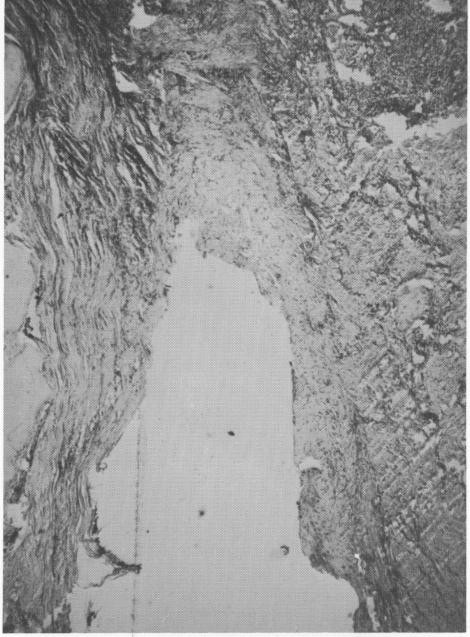

Fig. 4-32. A section from a failing implant. Note the in-filtration of inflammatory cells and the extra thickened granulation tissue.

Case 3. This case was considered to be a total failure because the implant was loose from the very beginning due to poor operative techniques. Even though loose, the implant remained in the patient's mouth for 14 months and caused no pain. Upon removal, the implant was sent to Harry Lane Robin-son, M.D., New York University School of Dentistry. His report follows (Fig. 4-32).

MICROSCOPIC: Sections of the soft tissue segments reveal a relatively dense, but active, fibrous tissue supporting a very distorted and crevicular type of epithelium. The epithelium exhibits considerable spongiosis in most areas. There is a rather minimal but diffuse chronic inflammatory infiltration with only a few areas of rather discrete heavy infiltration. In these latter areas there are plasma cells and lymphocytes predominate. Some of the fibroblasts are moderately active, and most of the collagen bundles are relatively immature. In the sections studied, there is no evidence of malignancy.

DIAGNOSIS: Fibrosis and chronic inflammation with crevicular type epithelial proliferation.

1 Histologic section from a failing Chercheve spiral-post implant